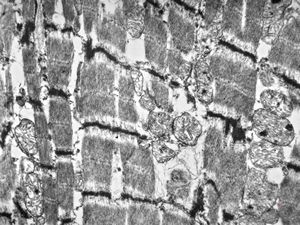

normal cardiomyocyte … transversal section (m … mitochondria, a … actin, my … myosin, arrow … tubules of s